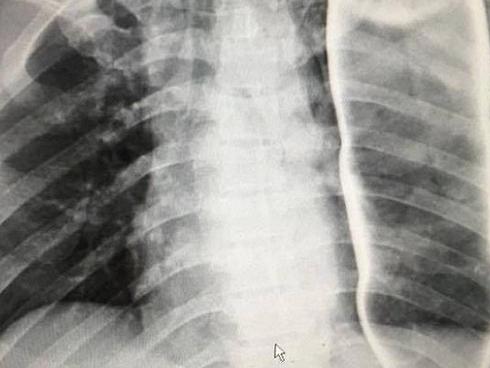

"Do xe đang di chuyển nhanh nên lúc nạn nhân nhảy xuống xe đã va chạm mạnh với mặt đường. Sau đó, được mọi người đưa đi cấp cứu Bệnh viện Đa khoa tỉnh Gia Lai, nhưng đến chiều tối cùng ngày nạn nhân đã tử vong", một điều tra viên nói.